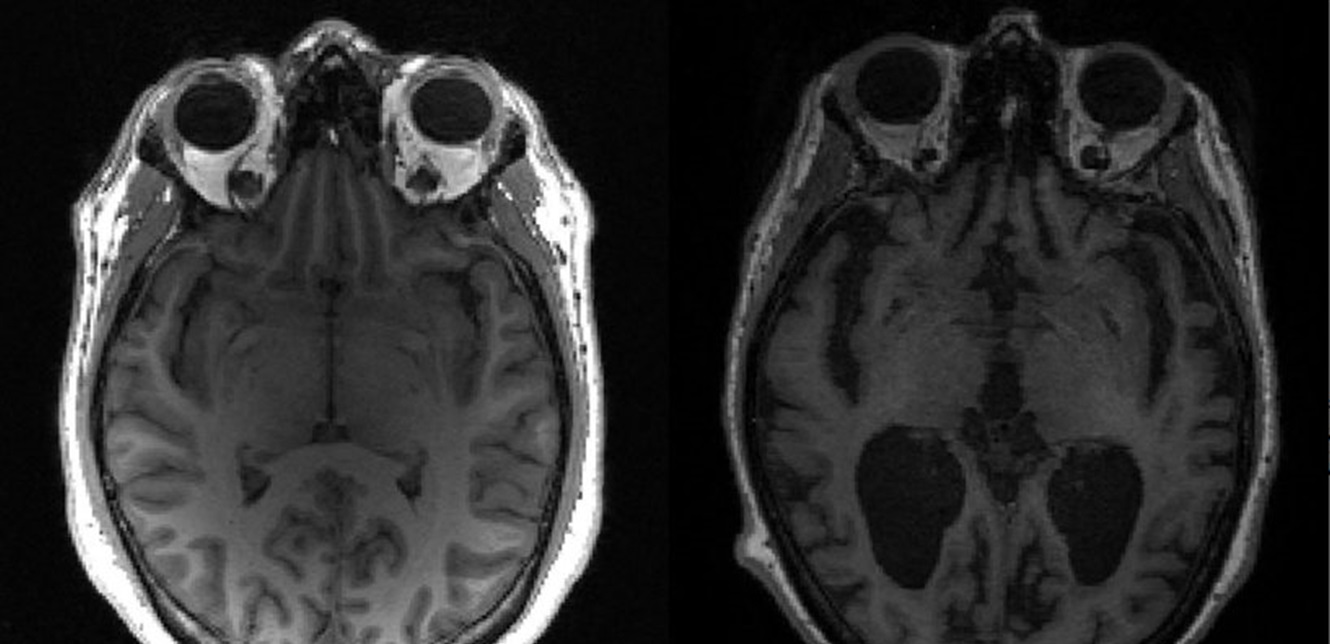

ومن خلال دراسة أنسجة المخ للأشخاص المصابين بالخرف بعد وفاتهم، وجد الباحثون سلسلة من ردود الفعل للأحداث التي تسببت في تلف جسور "المادة البيضاء"، التي تربط أجزاء مختلفة من الدماغ.

يبدأ التلف بالمايلين، الذي يشكل دروعا واقية، للحفاظ على حماية الخلايا العصبية ومساعدتها على التواصل بشكل أكثر كفاءة.

وعندما تصبح طبقات المايلين مهترئة، ويرجع ذلك جزئيا إلى الشيخوخة، وعوامل مثل ارتفاع ضغط الدم، تتم إزالتها من الدماغ بواسطة خلايا مناعية، تسمى الخلايا الدبقية الصغيرة.

واكتشف الباحثون أن الخلايا الدبقية الصغيرة نفسها يتم تدميرها أيضا، لأنها تجرف المايلين التالف.

ويبدو أن التأثير المتتالي لموت الخلايا الدبقية الصغيرة وتنكس المادة البيضاء، يلعب دورا في التدهور المعرفي المرتبط بمرض الزهايمر، وفقا للدراسة.